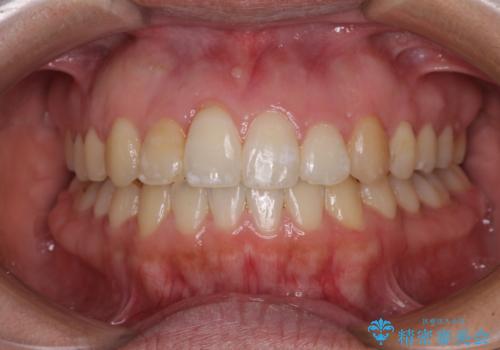

- 上下前歯の後戻りを気にして来院された患者様です。

インビザラインでの治療を希望されていて、デコボコの程度が中等度であり、安価なパッケージにて対応可能と判断されたため、インビザライン・モデレートを用いて矯正治療を行うこととしました。

インビザライン・モデレートは、製作できるアライナーの枚数に制限があるため、移動可能な量に限りがあるものの、インビザライン・ライトよりも枚数が多いため、幅広い症例に対応可能です。